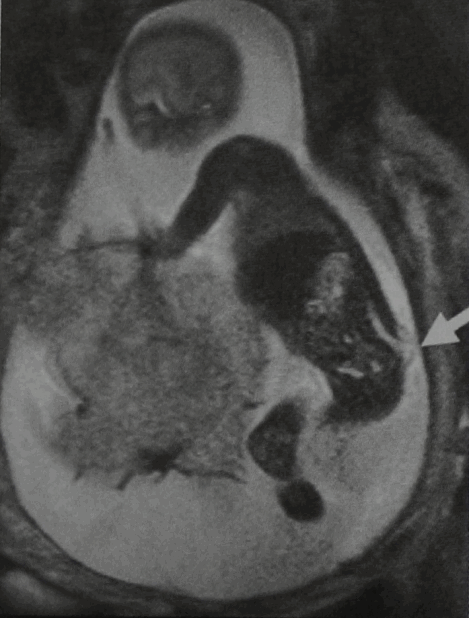

При УЗИ в 20 нед. беременности выявлено наличие spina bifida. МРТ плода и таза (фронтальная проекция, Т2-взвешенное изображение). Грыжевой мешок, расположенный в крестцовой области и содержащий структуры спинного мозга, ориентирован вдоль верхушки крестца.

На Т2-взвешенном изображении в горизонтальной проекции визуализируются костный дефект с широким основанием и миелоцеле, содержащее структуры спинного мозга (стрелка).